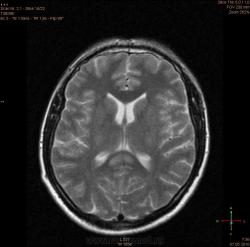

Болезнь Маркиафавы-Бигнами посмотри. На мой взгляд подходит.

Я заметил только 1 очаг в валике мозолистого тела. А для б-зни Маркиафавы-Бигнами более характерно несколько очагов дегенерации, в том числе и в полушариях.

Для болезни Маркиафава-Биньями считается патогноманичным центральная дегенерация мозолистого тела.

"Болезнь Маркиафава-Биньями – Болезнь Маркиафава-Биньями (Marchiafava, Bignami)- синдром при хроническом алкоголизме: энцефалопатия в форме центрального некроза corp.callosum (иногда и других комиссур). "

Я не против, действительно м.б. "Болезнь Маркиафава-Биньями". Особенно если нет динамики.

Но диф. ряд должен быть с опухолью. И если есть негативная динамика, тогда больше похоже на то, что в моз.теле не дегенерация, а "плюс-ткань" - обьемное образование. За октябрь сканов нет?

К сожелению первое исследование проводил ни я, а моя коллега, но контроль был за мной. Уже при первом исследовании, опухолевую принадлежность можно взять под сомнение, по скольку, даже допустим возьмем глиобластому это злокачественная опухоль из глиального ряда, т.е. должен быть тумор+отек=масс-эффект, ни того и не другого нет, ко всему этому сама локализация это валик мозолистого тела, а ни гемисфера, компенсации ни должно быть ни какой, клиника должно быть молниеносной и нарастающей.

Ко всему выше перечисленному могу добавить, видимо мою коллегу сомнения гложили, она провела исследование с контрастированием и получила тот же результат.

Контроль МР-исследования от октября я вложил, а что из себя представляет глиобластома, Корниенко В.Н. и Пронин И.Н. продемонстрировали: